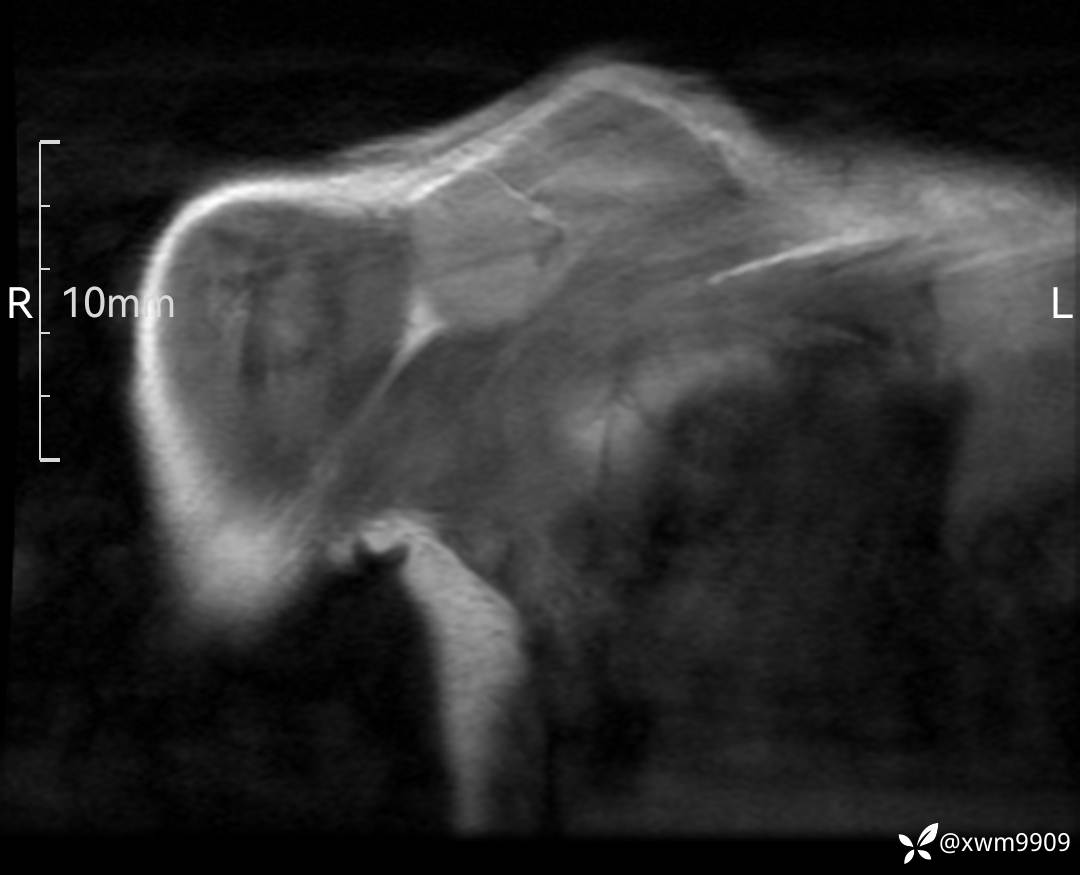

DR:

CT:

2、CT、MR肿块内可见液-液平面,常见有哪些疾病。